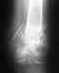

О ситуации на сегодня неизвестно ничего, а их возможных много. При отсутствии информации разговор бессмысленный. Покажите снимок для начала.